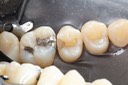

Scott Kanamori #14 caries removal